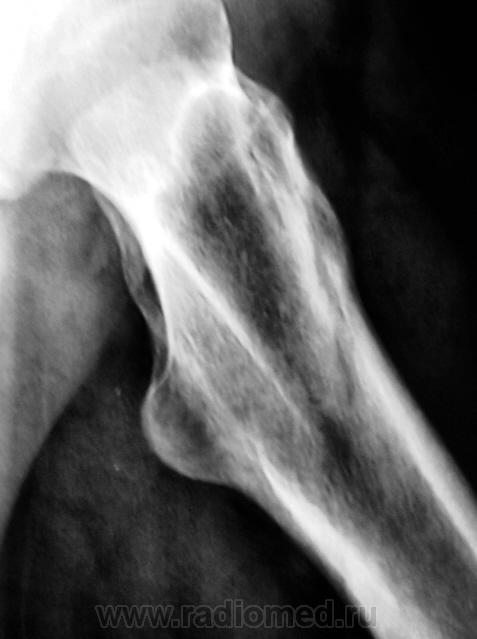

Следуюшая проекция.

Линия перелома косая, начало -сразу за шейкой а на противоположный контур кости -выходит ниже основания большого вертела... Хорошо, что практически без смещения.

Так и где же тогда такая полоска? То что имеем - это широкая, местами прерывистая полоса просветления по контуру большого вертела....как мне кажется (см.первые снимки), ведь срок уже после травмы немалый...

И часто ли приходится видеть такие "скромные" переломы шейки? Это еще один вопрос....